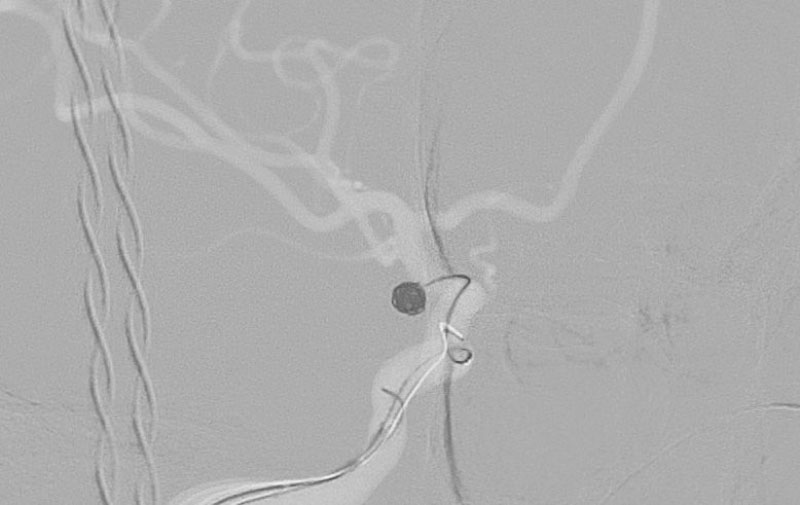

右内頚動脈後交通動脈

分岐部動脈瘤破裂

No.1593 手術後